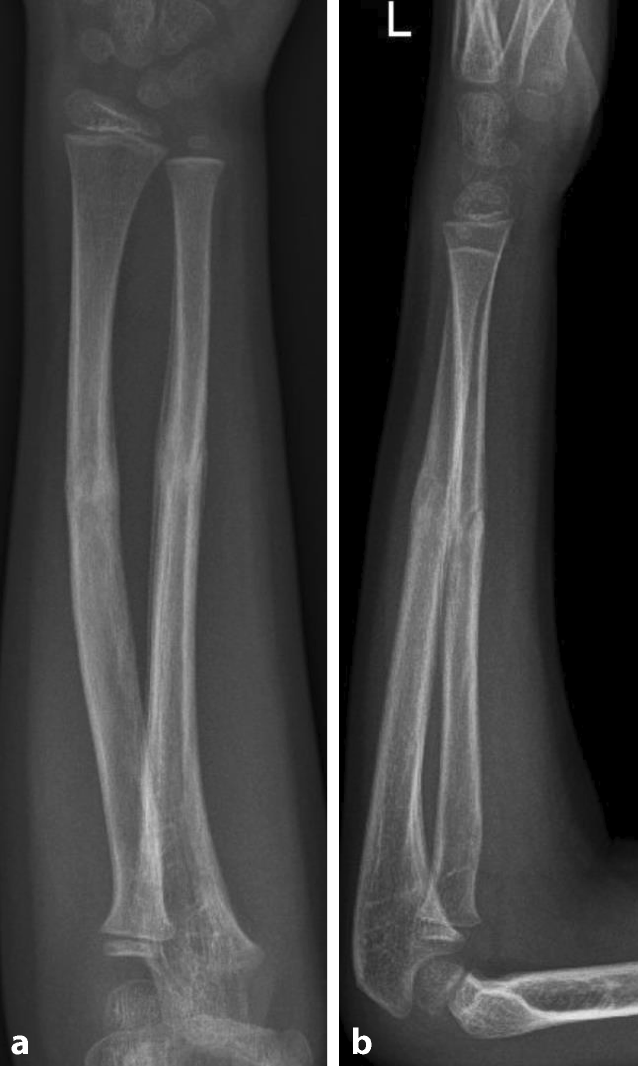

Abb. 6

Sankey-Diagramm mit Darstellung der erhöhten Rate von Refrakturen in nichtdurchgebrochenen Grünholzfrakturen

Der Anteil an Refrakturen war in der operativ behandelten Gruppe signifikant geringer, verglichen mit der konservativ behandelten Gruppe (operativ 6 von 186 (3,2 %) vs. konservativ 34 von 234 (14,5 %), p < 0,001, χ2-Test).

Um den Einfluss der initialen Behandlung bzw. des Durchbrechens der Gegenkortikalis näher zu beleuchten, wurde eine Subgruppenanalyse durchgeführt. Von den insgesamt 234 konservativ behandelten Frakturen wurden 59 Frakturen in gewichts- und altersadaptierter Analgosedierung durchgebrochen und 175 nicht durchgebrochen. In der Gruppe der komplettierten Frakturen kam es in 3,4 % der Fälle (n = 2) zu einer Refraktur und in der Gruppe der nichtkomplettierten Frakturen in 18,3 % (n = 32). Dieser Unterscheid war statistisch signifikant (p = 0,005, χ2-Test). Es wurden 138 der insgesamt 186 operativ behandelten Frakturen durchgebrochen und 48 nicht durchgebrochen. In der Gruppe der durchgebrochenen Gegenkortikalis kam es in 2,9 % der Fälle (n = 4) zu einer Refraktur und bei den nichtdurchgebrochenen Frakturen in 4,2 % der Fälle (n = 2). Dieser Unterscheid war statistisch nicht signifikant (p = 0,668, χ2-Test). Die Abb. 7 stellt diese Unterschiede grafisch dar.